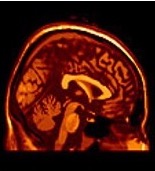

Which plane is depicted in the image below? Select the appropriate one.

plane